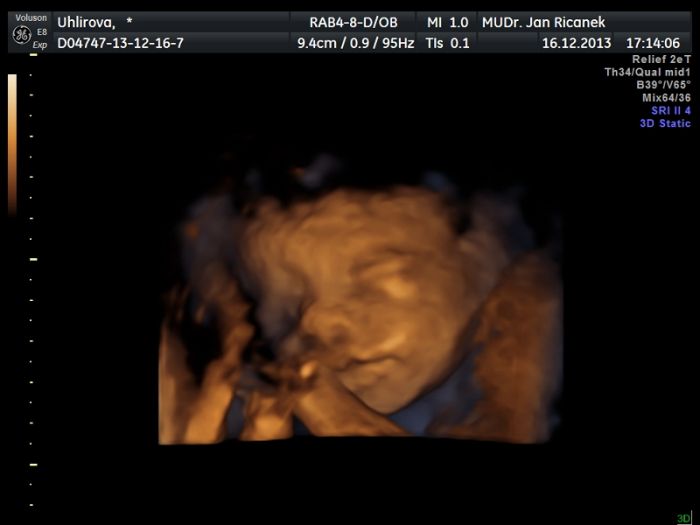

přidávám naši fotečku ze včerejška ze 3D